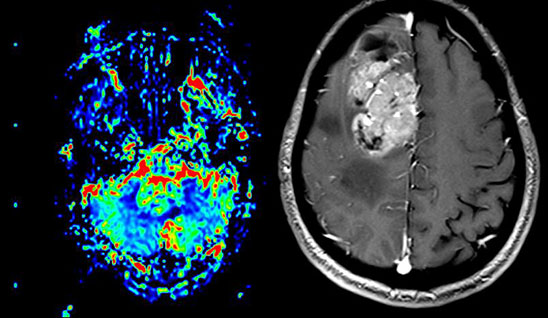

MAGNETOM Spectra 3.0T新一代聚能光谱磁共振

MAGNETOM Spectra 3.0T聚能光谱磁共振